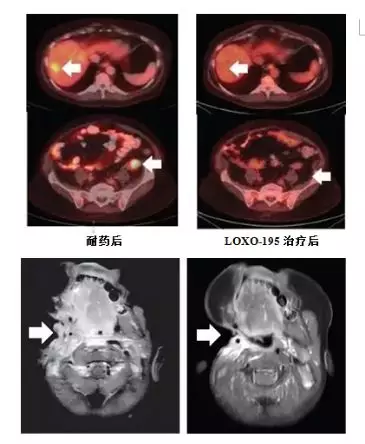

尽管,当前已经有一些参与拉罗替尼临床试验的患者出现了耐药。但可喜的是,依据拉罗替尼的耐药机制,第二代TRK靶向药物LOXO-195已经被FDA批准正式开展临床试验,专门来对抗耐药新突变,且已在部分耐药患者的治疗中取得了较好成效,具体如下: